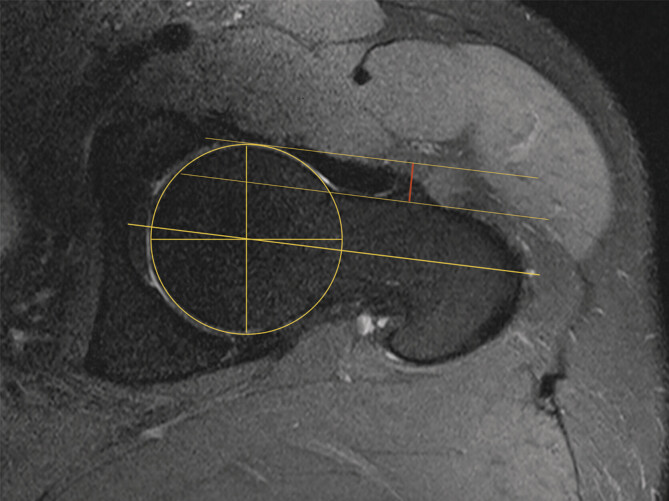

目的:x线,磁共振成像(MRI)和计算机断层扫描(CT)是确定股骨-髋臼撞击(FAI)头颈偏移(HNO)的标准方法。我们的假设是超声辅助确定髋关节CAM畸形的偏移量是一种便宜、无辐射、可靠的替代传统的α角测定方法。方法:在2015年1月至2019年12月期间,根据DEGUM标准程序和MRI进行前纵行髋关节超声检查的髋关节疼痛和疑似CAM撞击患者纳入本单中心研究。偏移量由两名独立调查员通过MRI和超声检查确定三次。结果:285例患者中,110例患者(女性49例,男性61例)符合纳入标准。54例左髋关节和56例右髋关节调查时的平均年龄为54.2岁。进行了1320次测量。MRI (6.11 mm+/-2.37)与超声(5.93 mm+/-2.20)检测HNO无显著差异。平均差值为0.32 mm±0.32 mm (p < 0.05),最大偏差为2.08 mm(异常值)。结论:超声辅助测定头颈偏移是一种可靠、可重复性高的方法,其准确性不低于MRI。超声检查最初可作为定性确定髋关节CAM畸形的替代或附加工具。

Purpose: Native X-ray, magnetic resonance imaging (MRI), and computed tomography (CT) are standard methods for determining head-neck offset (HNO) in femoro-acetabular impingement (FAI). Our hypothesis was that sonography-assisted determination of the offset in CAM deformity of the hip is a cheap, radiation-free, and reliable alternative to conventional alpha-angle determination.

Methods: Patients with hip pain and suspected CAM impingement who underwent anterior-longitudinal hip sonography according to DEGUM standard procedures and MRI were included in this single-center study between January 2015 and December 2019. Offset was determined three times on MRI and sonography by two independent investigators.